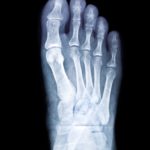

Since your feet are comprised of a number of different small bones, they can fracture in multiple places or at odd angles when exposed to acute trauma. Sometimes the best way to ensure that these bones and joints heal correctly is by inserting plates, screws or other hardware. Some of these pieces stay in your […]